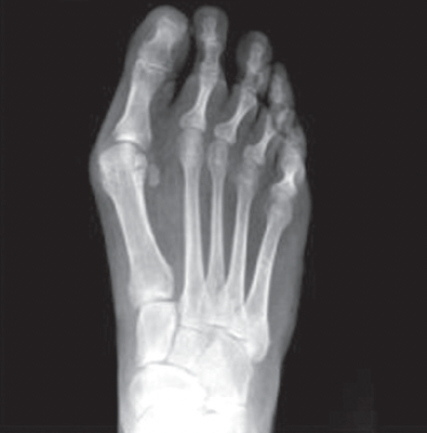

BEFORE

AFTER